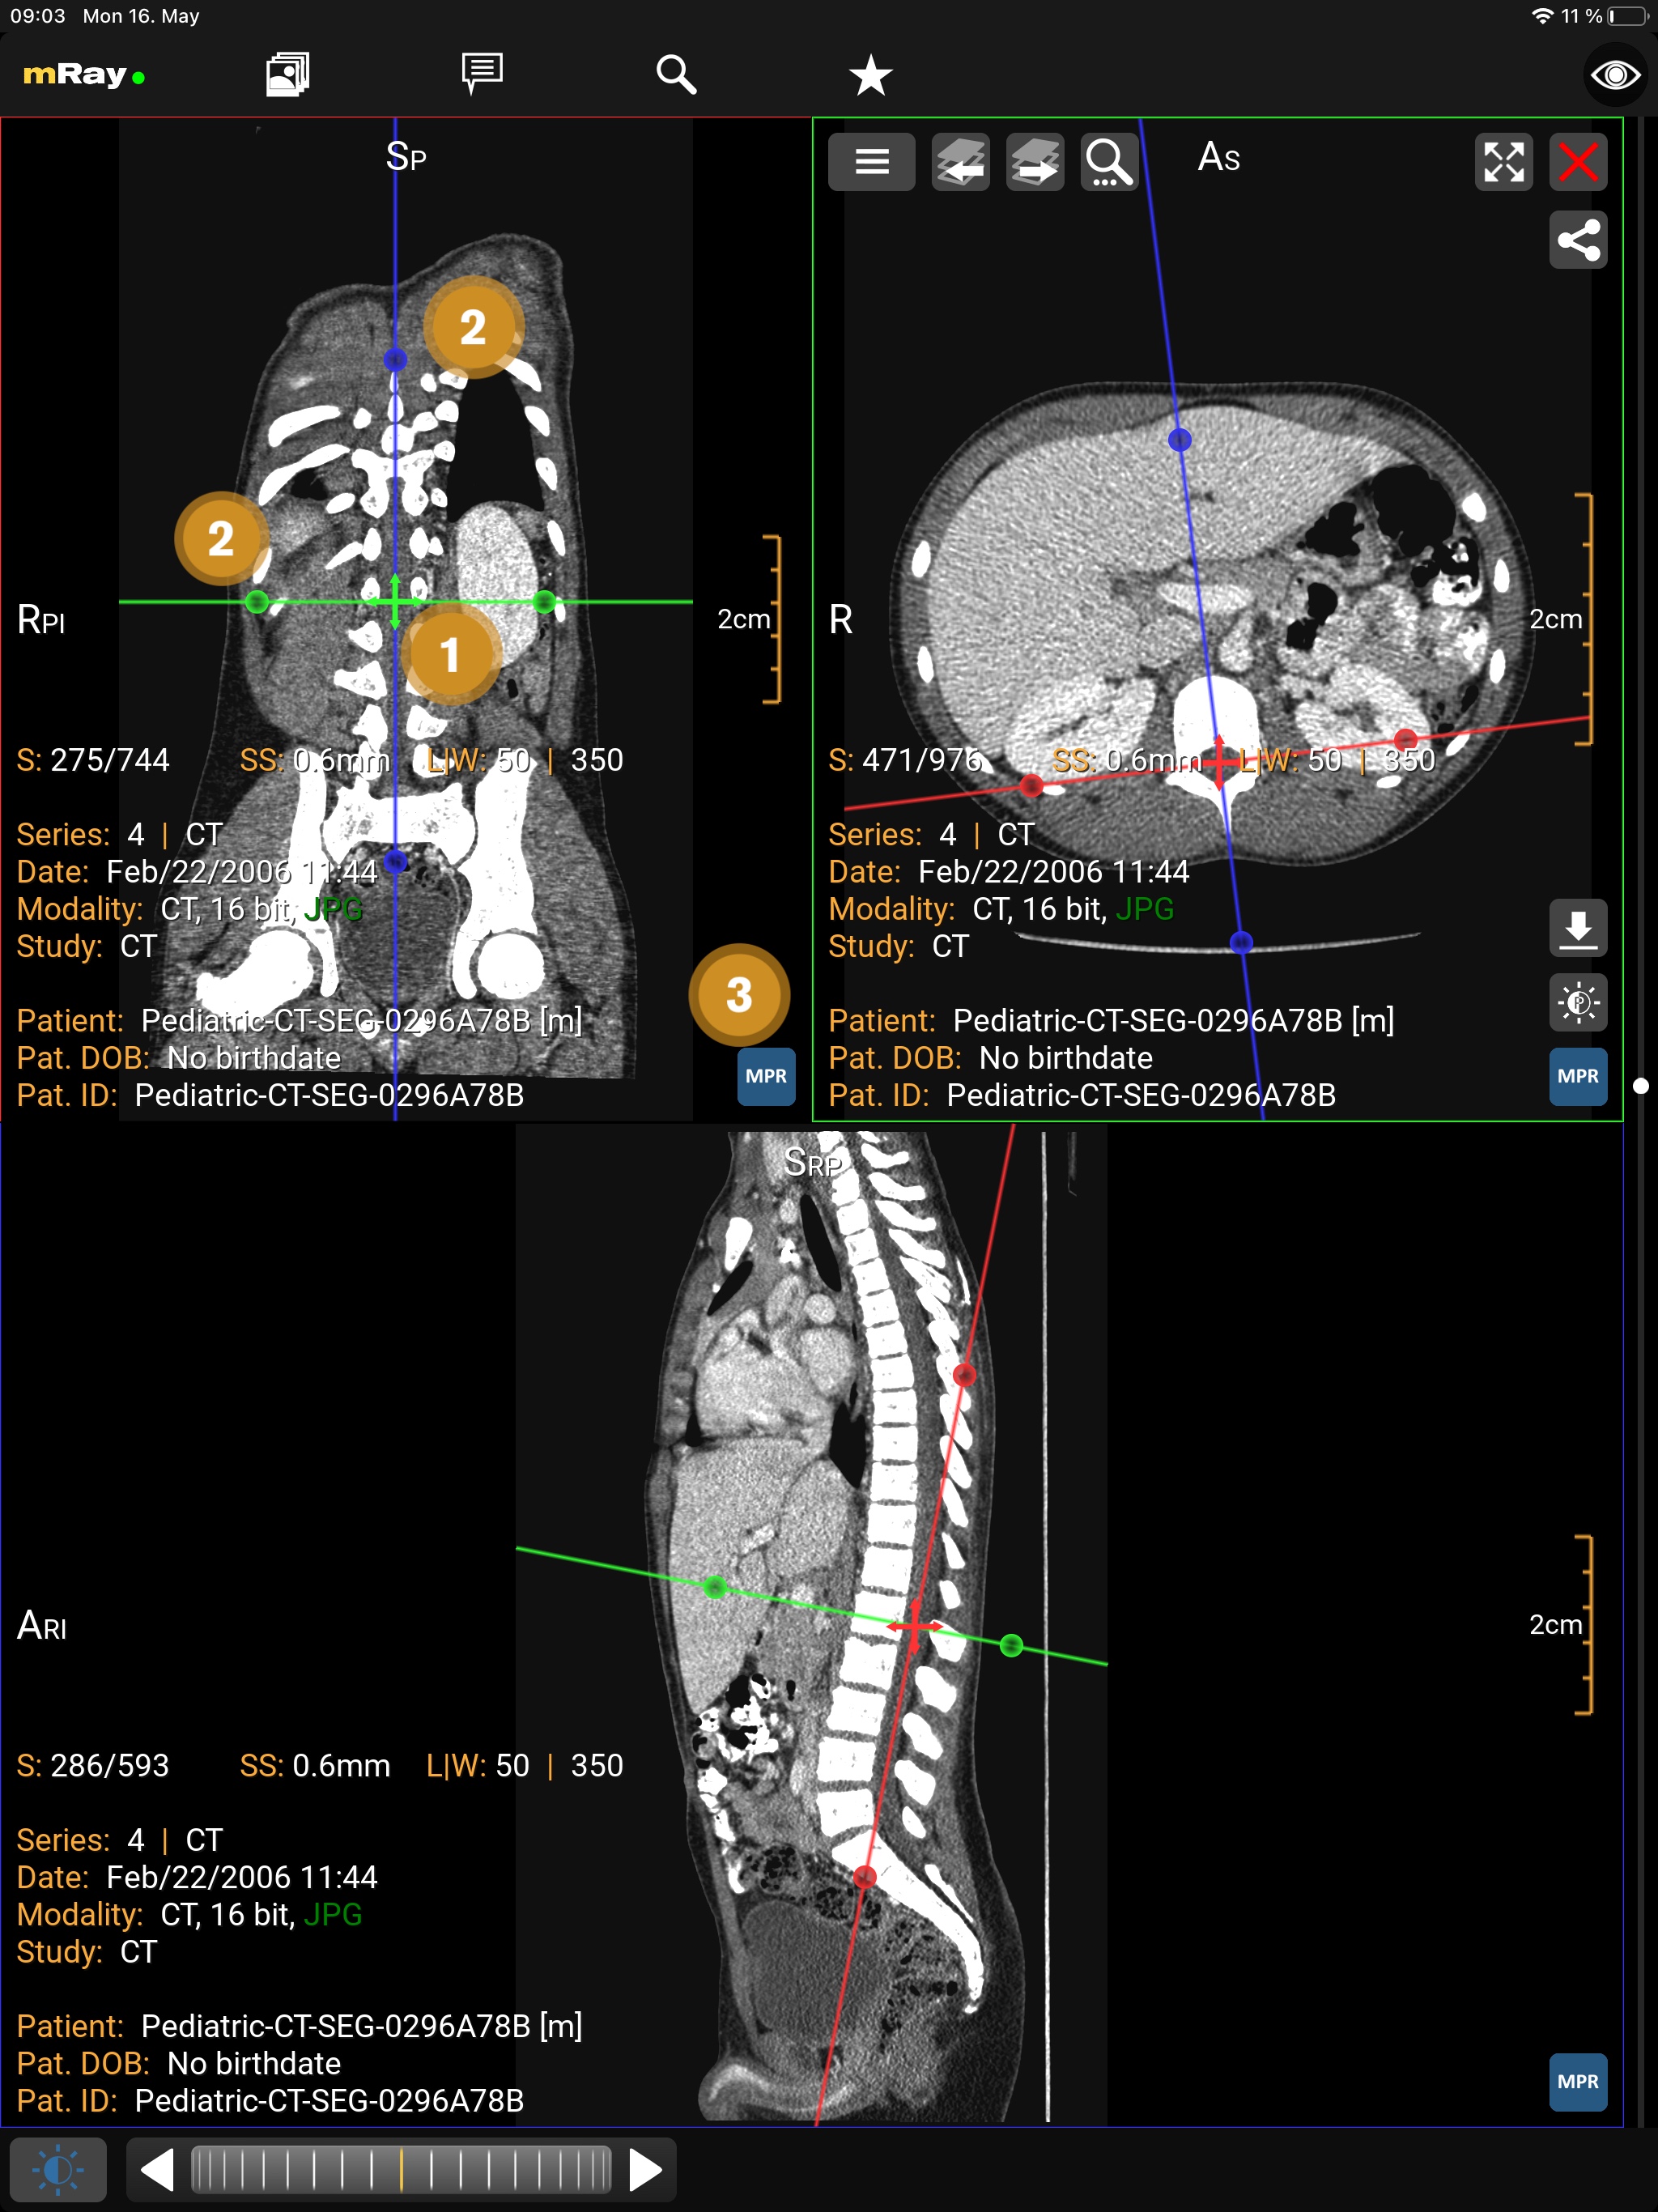

The MPR views allow you to open up multiple views at once ([abbr-mpr] View). Following screenshot shows the MPR view:

The Screenshot shows the original view of a dataset, the locally computed reconstructions (MPRs) and information to the viewed dataset.

-

Add more views here

.

The maximum number of views is 2 on smartphones and 4 on tablets.

Temporarily display view in a fullscreen state and back to previous state using maximize

.

The maximum number of views is 2 on smartphones and 4 on tablets.

Temporarily display view in a fullscreen state and back to previous state using maximize  and minimize

and minimize  icons.

icons. -

Indication of the current view direction in relation to the original image stack. You can change the view direction by pushing this button

.

. -

Use this button

to synchronize with the active view.

See Synchronized Views for more details.

to synchronize with the active view.

See Synchronized Views for more details. -

Shows the reference lines depending on the other opened views. These can be configured in the Toolmenu

You can change the perspective with the MPR perspective button (Point 2). This allows you to switch between axial, sagittal and coronal. The button in the top right corner (Point 1), allows you to open or close a view. If there is more than one view, a button to synchronize view adjustments will appear (see Synchronized Views). In order to interact with a view you have to select the appropriate view first. Therefore tap on the view. The selected view will be highlighted.